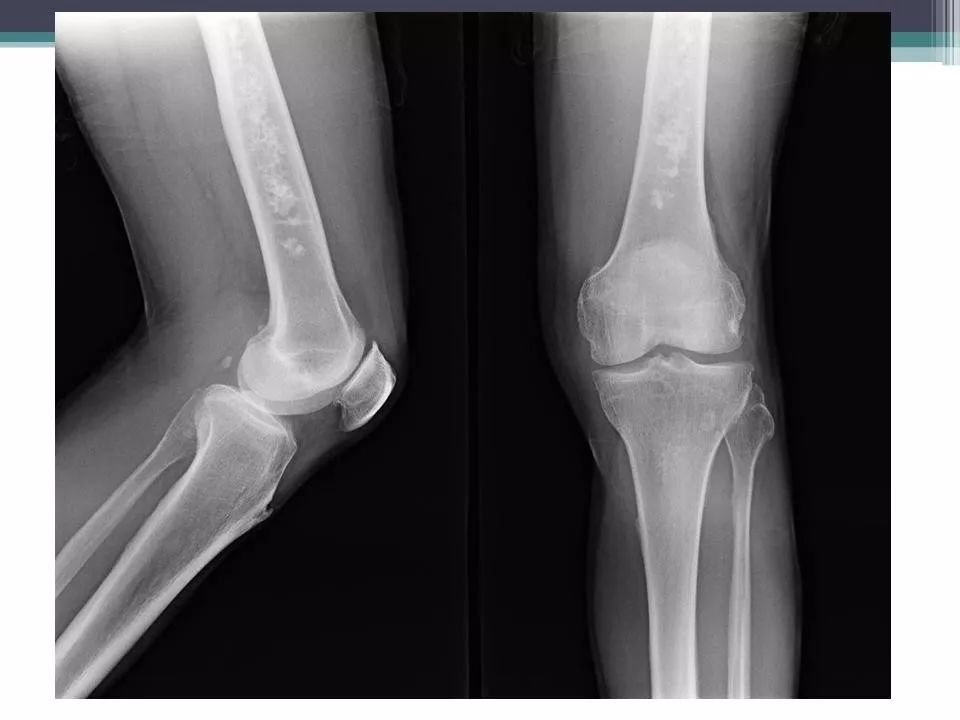

骨梗死的x片,比较少见哦